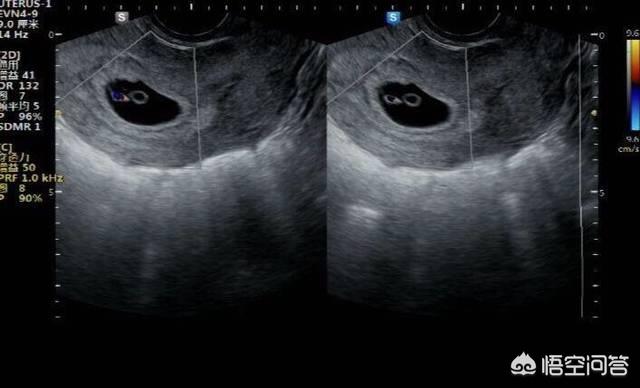

怀孕4周时,受精卵才着床成功; 怀孕5周时,受精卵着床成功后一边快速进行细胞分裂,一边向四周扩展,而这些细胞将会形成羊膜和血管包裹住 卵黄囊,胎儿就是从卵黄囊开始发育的。 在卵黄囊的外面是孕囊,孕囊是原始的胎盘组织。 所以, 一般在怀孕56周,可以做B超看到孕囊和卵黄囊,月经规律的女性,最早在怀孕35天时可以通过阴超看到孕囊; 怀孕67周时,可以通过B超看到胎3 怀孕5周孕囊大小多少是正常的 1、4周:胎儿只有02厘米。 受精卵刚完成着床,羊膜腔才形成,体积很小。 超声还看不清妊娠迹象。 2、5周:胎儿长到04厘米,进入了胚胎期,羊膜腔扩大,原始心血管出现,可有搏动。 B超可看见小胎囊,胎囊约占宫腔不到1胎芽特征 怀孕的第一个月为胎芽期,新生命在此期的成长速度是其一生中最快的。 妊娠第二周末精卵结合,受精后约4天,分裂成细胞团的精卵沿着 输卵管 到达子宫。 第三周,细胞团脱去外膜,为着床作准备。 第四周,胚泡已牢固地植入子宫里。 在这个

怀孕4周左右,B超看不到胎囊 患者信息:女 30岁 广东 珠海 病情描述 (发病时间、主要症状等): 怀孕4周,B超看不到胎囊,医生说有可能宫外孕,但是下腹一直没疼痛,也没出血! 月经最后一天是1254但是只有1264那一天同房一次就怀孕了,这样应该是怎么 9周 2.15厘米 此时胎囊几乎占满宫腔,胎儿各部表现更清晰,胎盘开始出现。 10周 2.厘米 这个时段胎囊开始消失,胎儿各器官均已形成,胎儿活跃在羊水中。 11周 3.62厘米 胎儿各器官进一步发育,胎盘发育,b超可见胎囊完全消失,胎盘清晰可见。 12周 458厘米 胎儿各脏器趋 6周 4,hcg,只有少许胎芽,没有胎心 查看 回复 29 t 发表于 2211 1645 来自疯狂造人 举报 29 楼主 直达 楼 谢赞,祝你好孕快快来 已邀请用户 : (此提示只有您可以看到,其他用户无法查看)